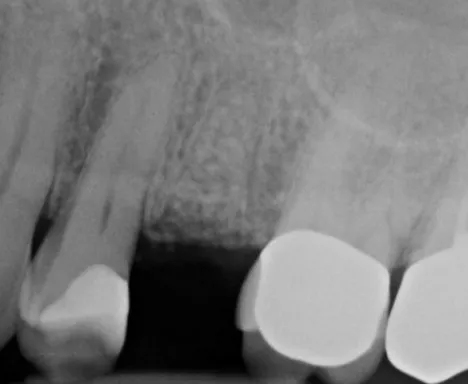

Dr.-Geivelis_Fig.2

Fig. 2. X-ray image taken after placement of Cytrans® Granules (S size) and allograft mixture.